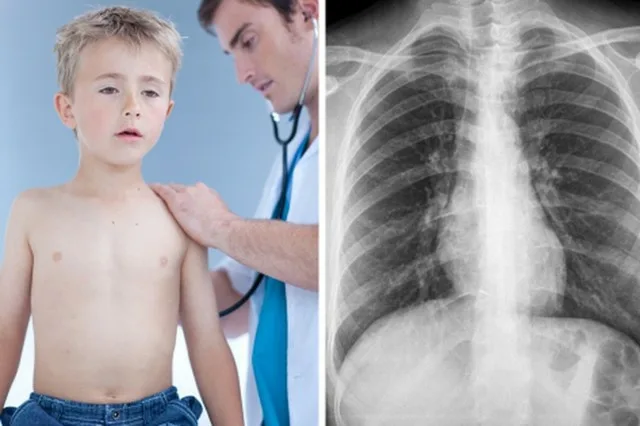

Пневмония в педиатрии — это серьезное инфекционное заболевание, которое затрагивает легкие и может вызвать множество осложнений. У детей, особенно у новорожденных и дошкольников, течение пневмонии существенно отличается от такового у взрослых.

Это связано с особенностями детского организма, который еще не полностью сформирован и имеет свои уникальные реакции на инфекции. Пневмония у детей может привести к высоким процентам неблагоприятных исходов, поэтому важно знать симптомы и причины этого заболевания, а также методы диагностики и лечения.

Симптомы пневмонии у детей могут варьироваться в зависимости от возраста. Чем младше ребенок, тем менее типичными могут быть проявления болезни. У новорожденных и малышей симптомы могут быть неочевидными, и на первый взгляд могут напоминать обычную простуду.

Кроме того, дыхание становится учащенным, и сердце начинает биться быстрее. Кашель может отсутствовать или появиться только на 5-6 день болезни. У ребенка также могут возникать тошнота и рвота, а иногда и диарея. На рентгенограмме могут быть видны очаги затемнения, а при массивном поражении одна половина грудной клетки может отставать в дыхании. При прослушивании легких может быть слышно жесткое дыхание с множеством хрипов.

Отдельно выделяются внутрибольничные пневмонии, которые развиваются у детей в первые три дня жизни. Они протекают тяжело, с выраженной интоксикацией и дыхательной недостаточностью. На рентгене могут не наблюдаться типичные изменения, а клиническая симптоматика может быть скудной.

При подозрении на пневмонию у ребенка необходимо срочно обратиться к врачу. Госпитализация является важным шагом для проведения полного обследования.

— Рентгенография легких для выявления характерных очагов.